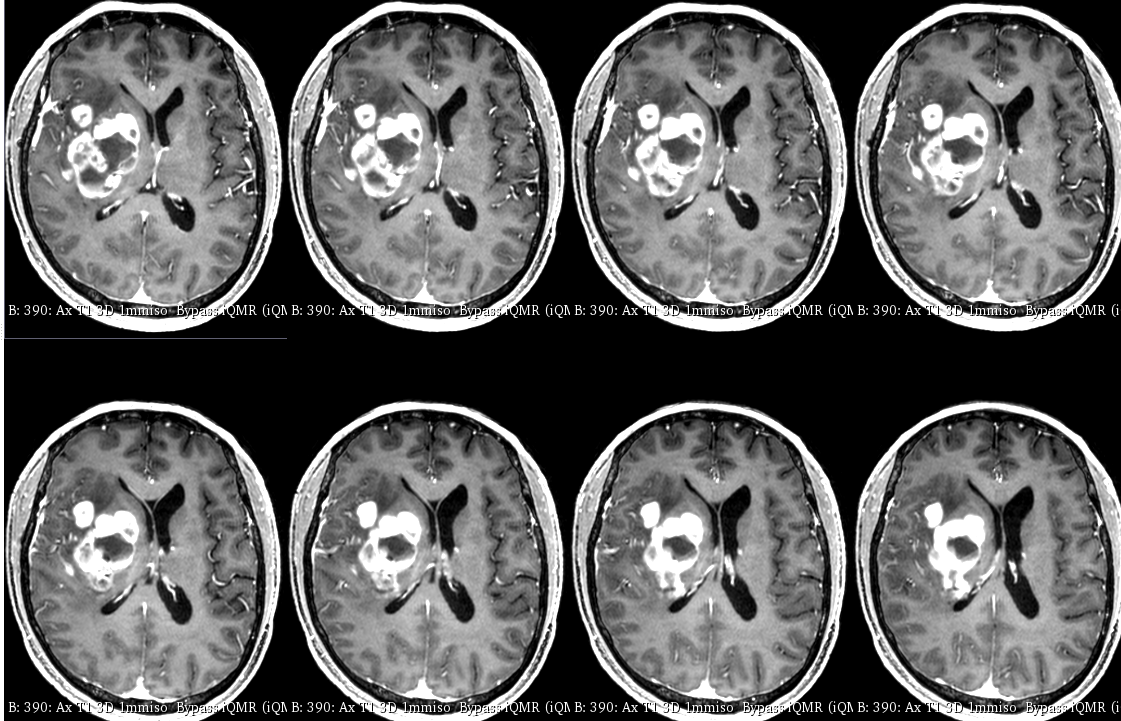

入院后于当地医院完善头颈部CTA检查未见明显血管发育异常,于2023-6-7行血肿钻孔引流术+脑室内颅内压监护探极置入术,引流一周后拔除引流管,期间未行尿激酶注射,患者反应情况逐渐好转,肌力未见明显改善。于出血后3周左右脑水肿基本消退后出院行康复治疗,治疗过程中患者肌力曾有所改善,左侧肢体肌力最好可达3级。术后3月左右患者一般状态逐渐变差,无发热,神志逐渐进展为昏睡状态,左侧肢体肌力1级,复查颅脑CT示水肿较前明显加重,颅脑MRI示右侧基底节区长T1长T2团块状病变,内有囊变,呈不均匀菜花样强化,考虑为高级别胶质瘤可能性大。遂行开颅病灶大部切除+去骨瓣减压术,术后病理提示高级别胶质瘤伴囊变,后续行同步放化疗STUPP方案,PTV:60Gy/30F/6周,替莫唑胺350mg化疗。患者右侧基底节区病灶相对稳定,2024-9-3复查颅脑MRI可见脑室内新发病灶。患者目前KPS 60分,神志清醒,精神差,反应迟钝,语言对答部分切题,右侧肢体自主活动,左侧肢体肌力2级。